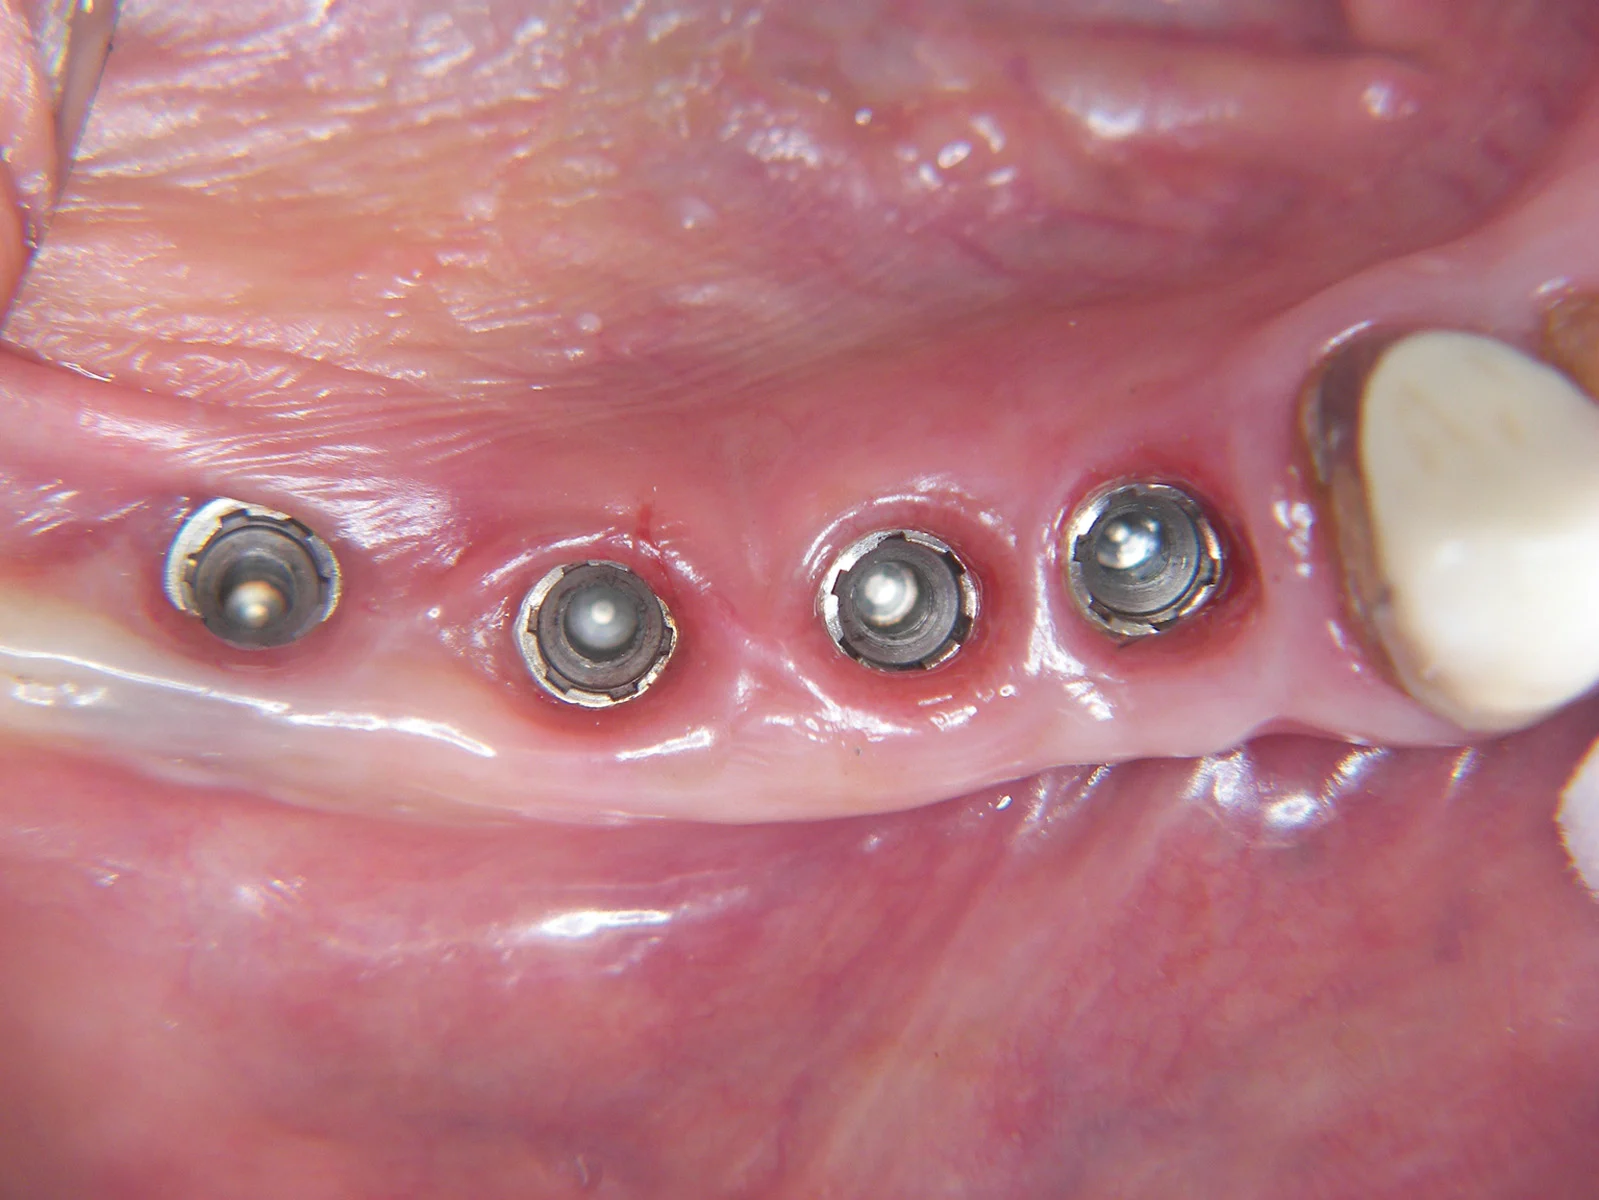

Se il paziente non desidera sottoporsi a chirurgia, si può optare per protesi rimovibili parziali o totali, eventualmente stabilizzate con mini-impianti.

Sono una soluzione meno invasiva, più economica e con tempi di realizzazione ridotti.

Alcuni pazienti scelgono questa via in attesa di un miglioramento delle condizioni cliniche o economiche che permetta un futuro trattamento implantare.